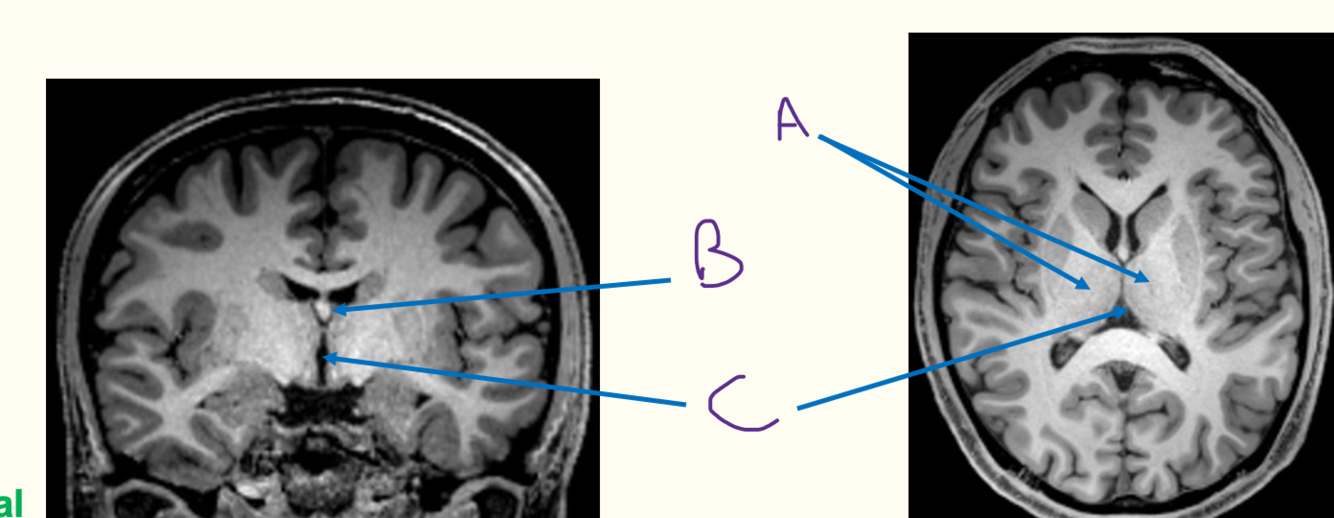

i) label the diagram

A = fornix B = septum pellucidum

C = corpus callosum

D = caudate nucleus

E = hippocampus

F = thalamus

G = lentiform nucleus

ii) Lentiform nucleus is mde up of the putamen and globus pallidus

i) communication between the third and fourth ventricle

ii) aka he aqueduct of sylvius

iii) surrounded by the midbrain

iv) A = third ventricle

B = fourth ventricle

C = cerebral aqueduct